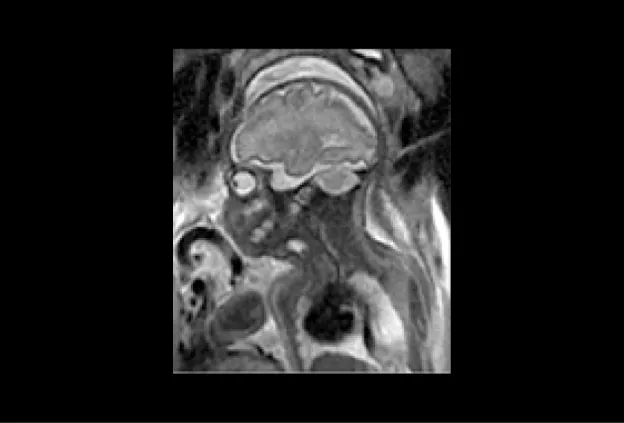

MRI image of a 30 week fetus shows normal fetal brain on this sagittal image (acquired in the midline of the brain). Notice how much detail can be seen of the foldings (sulci and gyro) of the brain, the brain stem, and the cerebellum.